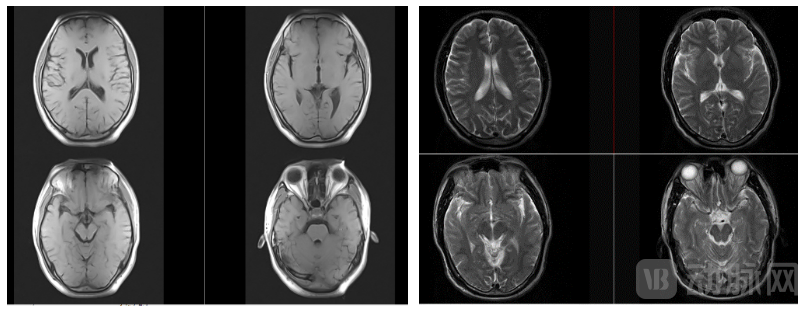

中科微影0.2T移动式头颈核磁成像效果